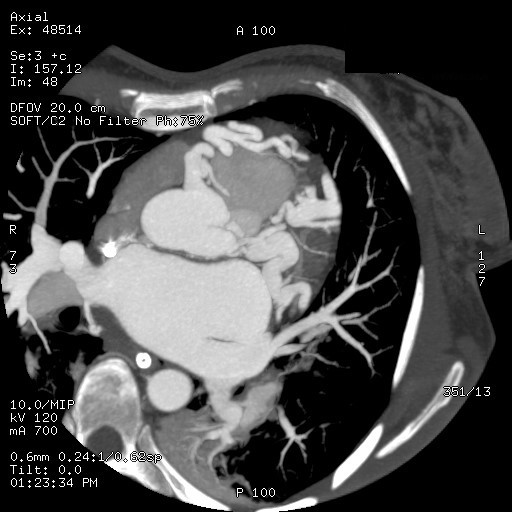

Background Out-of-hospital cardiac arrest is a major cause of mortality, most commonly related to ischemic heart disease. Rare congenital coronary anomalies may represent an uncommon but potentially lethal substrate for malignant ventricular arrhythmias. Case Presentation A 42-year-old woman with no known cardiovascular history was found unconscious in an out-of-hospital setting. On arrival of Emergency Medical Services, she was in cardiac arrest due to ventricular fibrillation. Electrical defibrillation restored spontaneous circulation(ROSC). Post-ROSC EKG showed a new-onset left bundle branch block. Urgent coronary angiography revealed a complex congenital coronary anomaly characterized by absence of the left main coronary artery and a single coronary artery arising from the right coronary sinus. The vessel appeared markedly ectatic and tortuous, giving rise to both the left anterior descending(LAD) and circumflex(LCx) arteries, without angiographically significant stenoses. Multiple coronary arteriovenous fistulas draining into the pulmonary artery and involving septal branches were also observed ( Image 1A ). Coronary CT confirmed the absence of the left main coronary artery and demonstrated a single ectatic coronary artery (up to 7 mm) originating from the right coronary sinus, with a highly tortuous course and formation of a vascular network at the cardiac apex. Retrograde filling of a dilated LAD and origin of a dilated LCx (7–8 mm) were observed ( Image 1B-C ). Multiple fistulous connections with hypertrophic bronchial arteries were present. A right-sided pneumothorax and pneumomediastinum were also detected and successfully treated with chest drainage. After a few days in the intensive care unit, the patient was weaned from mechanical ventilation with complete neurological recovery. Initial transthoracic echocardiography showed severe left ventricular systolic dysfunction (LVEF 30–35%), which improved to 60% during hospitalization. Given the occurrence of ventricular fibrillation in the absence of a reversible ischemic cause, a dual-chamber implantable cardioverter-defibrillator was implanted for secondary prevention. At discharge, the patient was prescribed only a beta-blocker. Conclusion This case highlights a rare presentation of complex congenital coronary artery anomaly with extensive coronary fistulization leading to sudden cardiac arrest. Advanced imaging and multidisciplinary management were essential for diagnosis and favorable outcome.